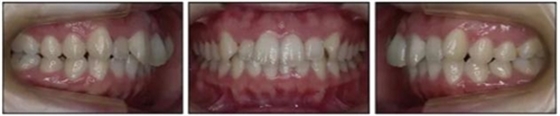

1.基本信息:女性,24歲2月,主訴上前牙及上唇不美觀(圖1)。因美觀問題不愿使用上頜固定矯治器。

2.檢查:凸面型、骨性II類,安氏II類1分類錯合畸形。面型正中對稱,下面高略高,頦部后縮,唇肌略緊張。無顳下頜關(guān)節(jié)癥狀,下頜運動正常,無偏斜。上下頜中線與面中線相一致,所有恒牙存在,口腔衛(wèi)生可,牙周情況可?;颊呓】?,無系統(tǒng)性疾病,無牙科創(chuàng)傷史及不良習(xí)慣,懷疑遺傳因素導(dǎo)致錯合畸形。

3.測量分析:治療前記錄提示該患者左右磨牙與尖牙為安氏II類關(guān)系,上頜牙弓重度擁擠,下頜牙弓輕度擁擠,深Spee曲線。6.3mm深覆蓋,80%深覆合。牙齒無齲,無第三磨牙。